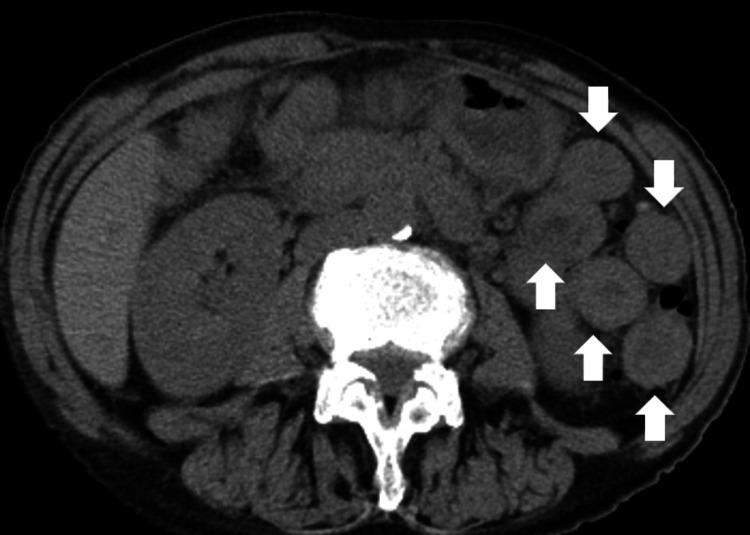

We report two cases of multiple white plaques in the esophagus that emerged after the administration of immune checkpoint inhibitors. Both patients developed enterocolitis as immune-related adverse events associated with immune checkpoint inhibitors. Esophagogastroduodenoscopy revealed duodenal involvement and multiple white plaques in the esophagus. A biopsy of the esophagus showed predominant CD3 lymphocyte infiltration, suggesting that esophageal mucosal alterations were associated with immune-related adverse events. In addition, histopathology showed keratinized stratified squamous epithelium in the first case while increased inflammatory cell infiltration in the intraepithelial and subepithelial layers was observed in the second case. These data suggest a different pathogenesis of the multiple esophageal white plaques between the two cases. Although further investigation is needed to elucidate the significance of these observations, recognition of the esophageal plaques may be important for prompt diagnosis of immune-related adverse events when associated with immune checkpoint inhibitors.